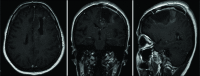

Case description: We present the case of a 41-year-old patient diagnosed with a left-sided frontal contrast enhancing lesion initially assessed as a tumefactive MS. Despite systemic treatment, the patient gradually developed signs of mass effect, which led to decompressive surgery. The initial microscopic evaluation demonstrated the presence of MS and oligodendroglioma; the postoperative evolution proved complex due to a series of MS-relapses and tumor recurrence. An ulterior revaluation of the samples for the purpose of this report showed an MS-concurrent anaplastic astrocytoma. We describe all relevant clinical aspects of this case and review the medical literature for possible causal mechanisms.